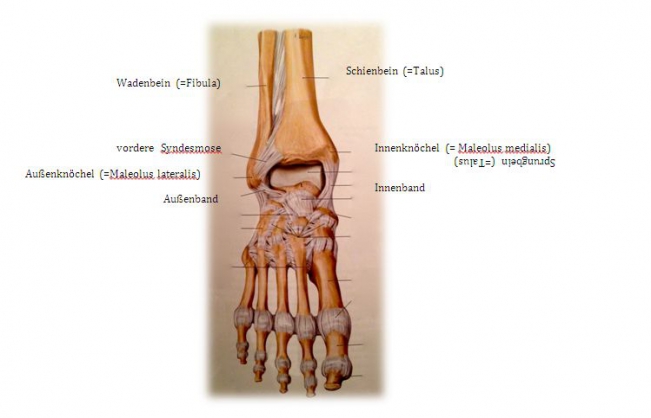

If one speaks of the ankle joint, one actually speaks of the "upper ankle joint". It is formed by three bones: Shin bone (= tibia), fibula and talus. Shinbone and fibula form a bony fork (= malleolus fork), which surrounds the anklebone in a U-shape. The upper ankle joint allows the foot to be raised and lowered.

The outer ankle is the joint process of the fibula, the inner ankle is the joint process of the tibia. A complex ligamentous apparatus ensures the stability of the ankle joint: outer ligaments, inner ligaments and anterior and posterior syndesmosis (= a very firm ligament connection between the tibia and fibula).

Fig.1) Anatomy of the upper ankle joint (from: Prometheus ®, MLP)